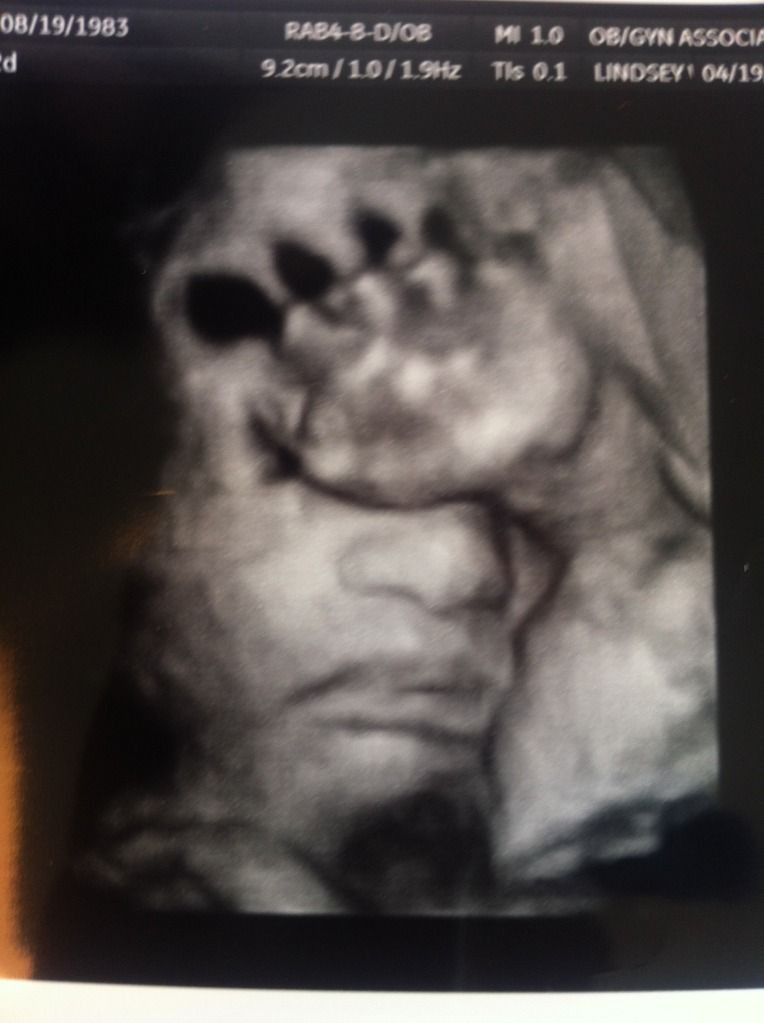

I feel like the worst mom ever because I never posted after our 28 week ultrasound. Let's chalk it up to my excitement. As I posted previously, the 20 week ultrasound reveal choroid plexus cysts on our little man's brain. We had an ultrasound at 28 weeks to check his brain. As expected, his little brain is PERFECT and the cysts are GONE. Praise God! While they were looking at his head, I saw 30w4d pop up on the screen. Considering I was only at 28w2d gestation at the time, not only is his head perfect, it's big! *shudder*

It appears he wasn't thrilled with us during the ultrasound. We must have been disrupting his nap. He wakes up like his daddy